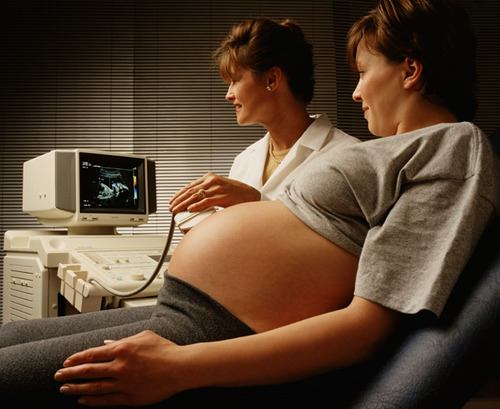

B超:像挑西瓜前敲一敲。B超利用的是超声波穿透人体,当声波遇到人体组织的不同部位时会产生不一样的反射波,通过计算反射波从而成像。就像挑西瓜一样,边敲边看显示病灶情况。除肠道外,腹部盆腔内基本都可以用B超检查。